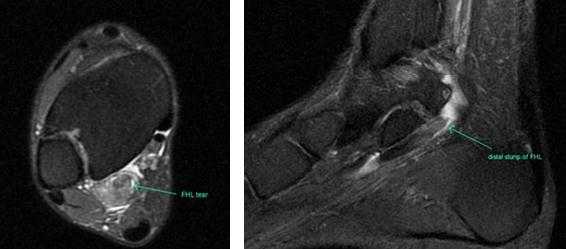

Прежде всего, это боль по задне-внутренней поверхности голеностопного сустава. Возможно «защёлкивание» большого пальца при его сгибании. Хруст, крепитация по задне-внутренней поверхности голеностопного сустава при активных движениях. При физикальном осмотре определяется боль при сгибании большого пальца через сопротивление, при форсированном подошвенном сгибании в голеностопном суставе, при этом боль отсутствует в области первого плюсне-фалангового сустава. Для диагностики повреждения сухожилия длинного сгибателя большого пальца стопы целесообразно выполнение МРТ, при этом обнаруживается скопление жидкости вокруг сухожилия на уровне голеностопного сустава, изменение сигнала от самого сухожилия.

Дифференциальная диагностика тендинита сухожилия длинного сгибателя большого пальца стопы проводится с тендинитами малоберцовых мышц, переломом заднего отростка таранной кости, заднюю таранно-пяточную коалицию, остеоид-остеому таранной и пяточной кости.

При разрывах сухожилия длинного сгибателя большого пальца помимо остро возникшей боли и отёка по задне-внутренней поверхности голеностопного сустава определяется выраженная слабость подошвенного сгибания большого пальца стопы.